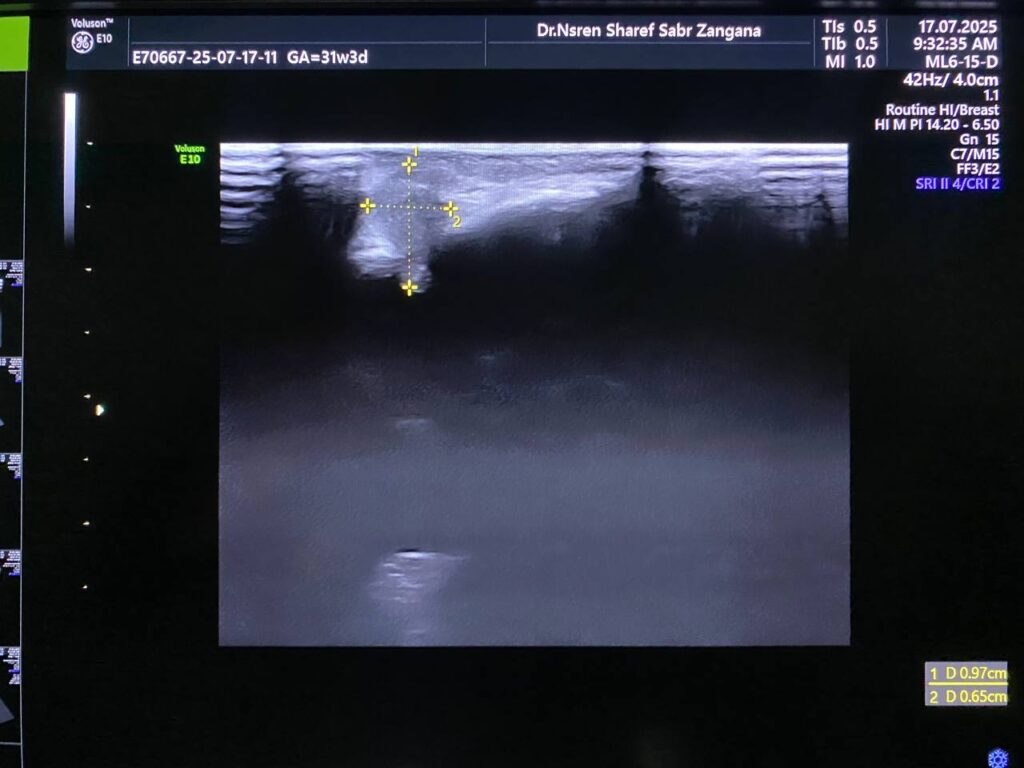

Associated with presence of of heterogenous mass 10x6mm , extruded from the brain tissue in the occipital region , mostly encephalocele